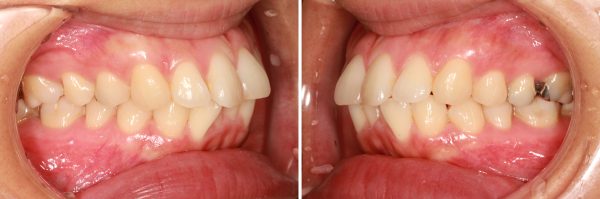

前歯が 出ています。 典型的な ”出っ歯” の状態です 少し段差もあります

前歯が 強く傾斜して、骨ごと 前に 出ています

上顎前突症(いわゆる 出っ歯)です

叢生を伴う 上顎前突症です

口もとの出っ張り、 前歯を下げるために上下顎左右の小臼歯抜歯を行い、前歯を後方に移動させました。

2023年9月6日にスタートして、2025年7月11日に終了しました。

治療期間は22か月でした。

抜歯を行ったことで、上顎の前後的な距離が適正になりました。

前歯が劇的に下がりました

同じように 下顎も前後的な距離が短くなり、適正な長さになりました。

上下歯列の長さが適正になった、この効果で上下の前歯が下がりました。

治療前後で前歯の傾斜がかなり改善しました。

レントゲン写真で確認しても上下の前歯は 大きく下がり、

前に出ていた上下の前歯の傾きが正常化しました。